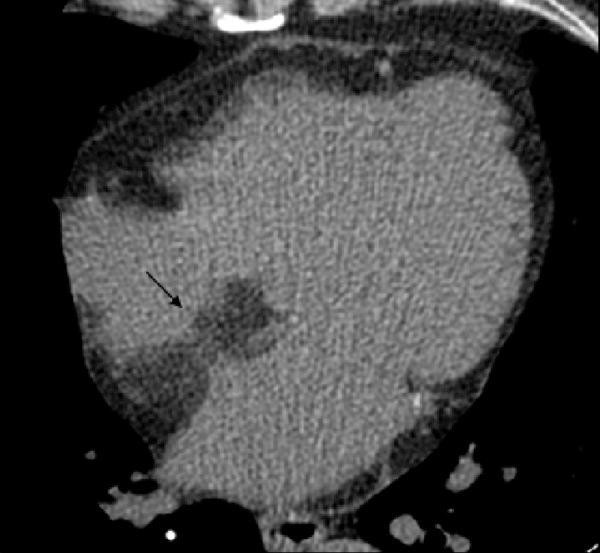

204 subjects (11.1%) had FR within the heart (113 men; 91 women; mean age 57.8 years); 66% of fatty foci were seen only in the native scanning. The distribution of the fat was: right ventricle (RV) 31.9%, left ventricle (LV) 21.5%, biventricular 39.7%, interventricular or atrial septum 5.9%, and atria 1%. In the RV, fat was localized mainly in the papillary muscles, while in the LV fat was mainly subendocardial (p<0.001). The morphology of the fat was: linear 61.6%, oval 14.8%, punctuate 10.6%, irregular 10.2%, and bilobular 2.8%. Fat was primarily located subendocardially in the LV in patients after myocardial infarction. In patients with suspected coronary artery disease, it was mainly observed subpericardially in the RV and in papillary muscles (p<0.001).

204例受试者(11.1%)心脏内存在FR(男性113例;女性91例;平均年龄57.8岁);66%的脂肪灶仅在平扫时可见。脂肪分布情况为:右心室(RV)31.9%,左心室(LV)21.5%,双心室39.7%,室间隔或房间隔5.9%,心房1%。在右心室,脂肪主要位于乳头肌,而在左心室,脂肪主要位于心内膜下(p<0.001)。脂肪形态为:线状61.6%,椭圆形14.8%,点状10.6%,不规则形10.2%,双叶形2.8%。心肌梗死后患者的脂肪主要位于左心室心内膜下。在疑似冠心病患者中,主要在右心室的心包下和乳头肌中观察到脂肪(p<0.001)。